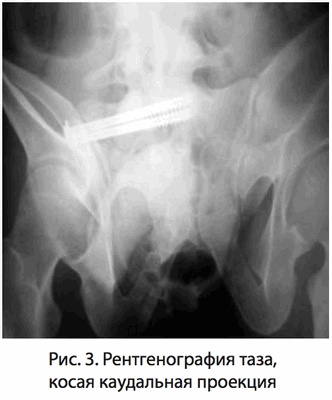

заведение канюлированных винтов проводилось под контролем электронно-оптического преобразователя в трех плоскостях - обзорный фасный снимок (рис. 1), краниальная (рис. 2) и каудальная (рис. 3) проекции. Это позволяет избежать повреждения сосудисто-нервных образований, располагающихся кпереди и кзади от ножки и тела s1 позвонка.